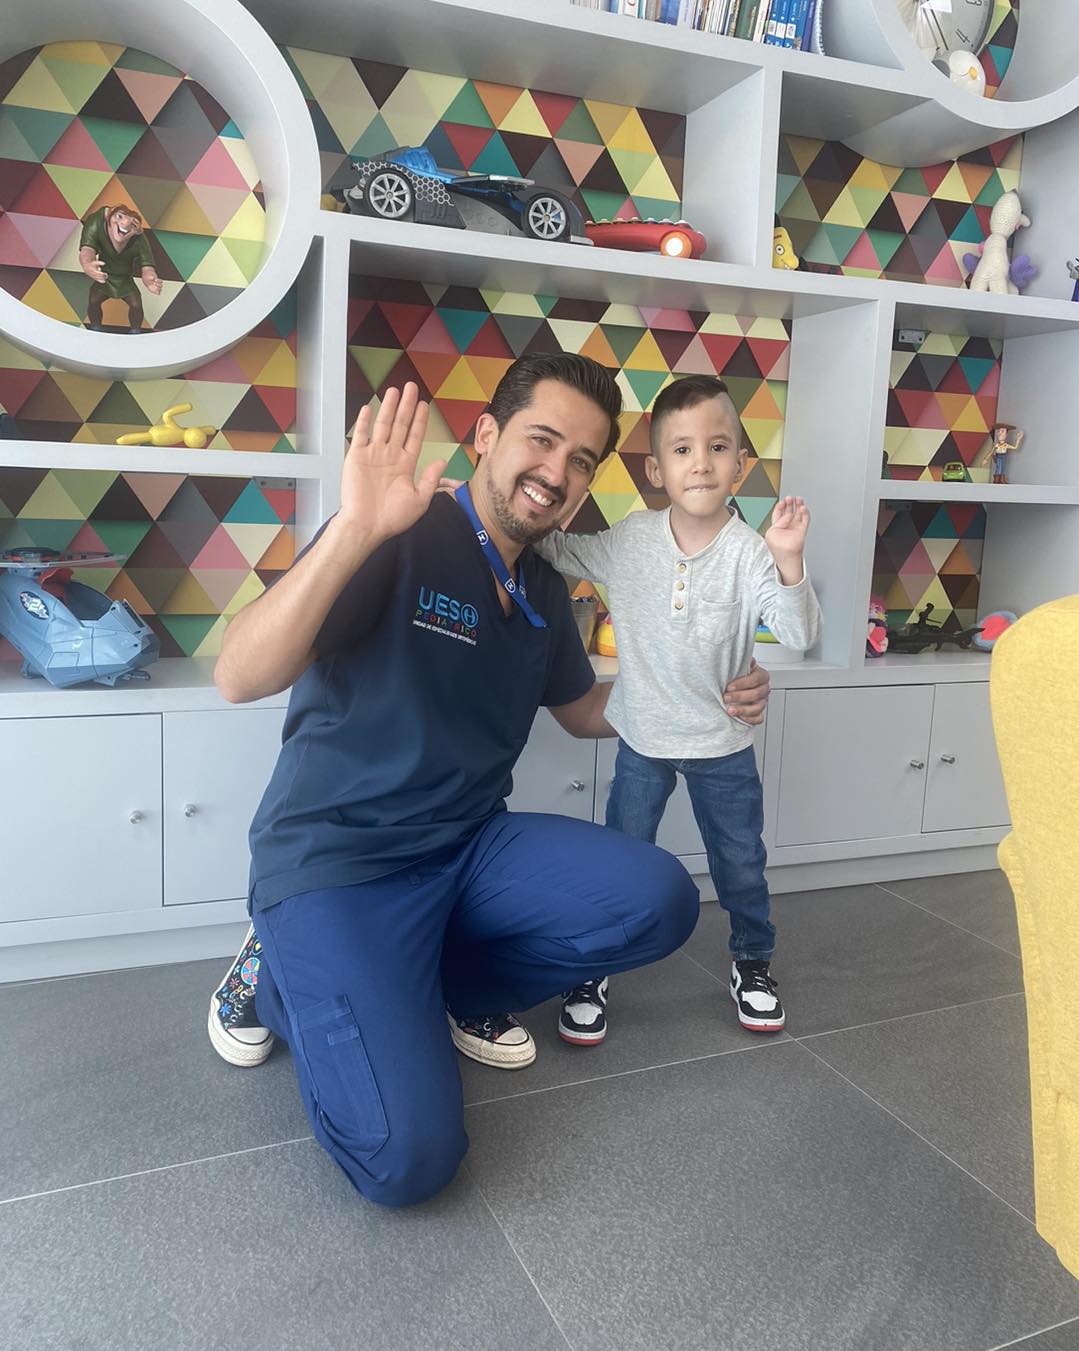

Atrogriposis con cadera luxada

Este superhéroe se llama Jesús Fernando y actualmente tiene cinco años. Nació con artrogriposis y con la cadera izquierda luxada. Recibió tratamiento en un hospital público, pero sin éxito; incluso la cirugía realizada fue fallida. Les comparto las fotografías de cómo llegó a mi consulta hace un año, y las imágenes después del tratamiento con yesos e intervenciones quirúrgicas: dos en los pies y una en la cadera. Mi valiente pacientito llegó sin poder caminar, ¡y ahora ya anda jugando por todos lados! Felicidades a sus papás por el esfuerzo para darle a Jesús Fernando este enorme regalo. Me siento muy agradecido por su confianza.